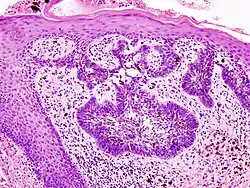

H&E stain

Hematoxylin and eosin stain (or haematoxylin and eosin stain or hematoxylin–eosin stain; often abbreviated as H&E stain or HE stain) is one of the principal tissue stains used in histology.[1][2][3] It is the most widely used stain in medical diagnosis[1] and is often the gold standard.[4] For example, when a pathologist looks at a biopsy of a suspected cancer, the histological section is likely to be stained with H&E.

H&E is the combination of two histological stains: hematoxylin and eosin. The hematoxylin stains cell nuclei a purplish blue, and eosin stains the extracellular matrix and cytoplasm pink, with other structures taking on different shades, hues, and combinations of these colors.[5][6] Hence a pathologist can easily differentiate between the nuclear and cytoplasmic parts of a cell, and additionally, the overall patterns of coloration from the stain show the general layout and distribution of cells and provides a general overview of a tissue sample's structure.[7] Thus, pattern recognition, both by expert humans themselves and by software that aids those experts (in digital pathology), provides histologic information.

Hematoxylin principally colors the nuclei of cells blue or dark-purple,[6][15][14] along with a few other tissues, such as keratohyalin granules and calcified material. Eosin stains the cytoplasm and some other structures including extracellular matrix such as collagen[5][7][14] in up to five shades of pink.[8] The eosinophilic (substances that are stained by eosin)[5] structures are generally composed of intracellular or extracellular proteins. The Lewy bodies and Mallory bodies are examples of eosinophilic structures. Most of the cytoplasm is eosinophilic and is rendered pink.[10][15] Red blood cells are stained intensely red.